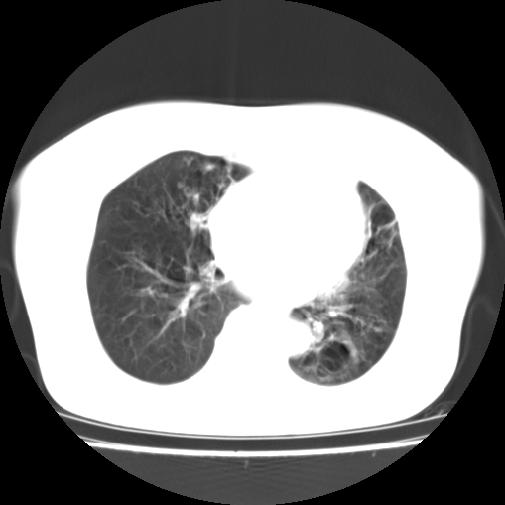

标题: CT16957:F56Y,这是先天性肺囊肿,还是支气管扩张??? [打印本页]

标题: CT16957:F56Y,这是先天性肺囊肿,还是支气管扩张???

女性病人,56岁,反复咳喘30余年,伴大量脓痰,偶有痰中带血。

此病例在科室里有较大的争议,我认为是先天性肺囊肿(理由是:两者起病年龄都较轻,都有咯血及脓痰的症状,而先天性肺囊肿壁薄;而支扩的囊腔旁一般都能看到伴行的血管影,形成“印戒”征)。以上为个人的意见,请高手们指点一下。

支持支气管扩张并感染,肺囊肿一般有较完整的囊壁。。。

影像符合支气管扩张伴感染,先天肺囊肿壁薄,而后天支扩因反复感染壁多较厚,有慢性支气管炎病史。最后诊断靠病理,先天肺囊肿的囊内无尘埃。

本例应为支气管扩张并感染,与囊肿区别在于其大小,分布,壁改变,与肺动脉关系,形态等来鉴别,要点大家都说得差不多了,囊肿要大些,分散些,靠外围一些,而支扩靠内一些,聚拢些,小一些且易聚拢呈葡萄状,不能单从囊壁厚度来评价,特别是有粘液栓类的改变更加支持支扩,有时支扩亦与囊肿混在一起并存.个人意见仅供参考.